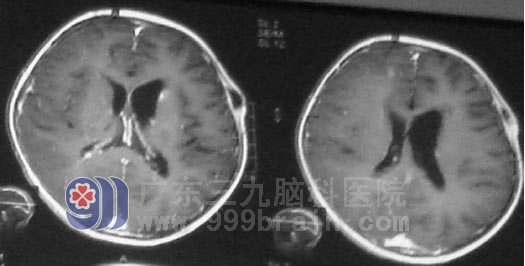

生殖细胞瘤为低度恶性肿瘤,对放射线非常敏感。小勇在 肿瘤综合治疗中心接受放射治疗。虽然肿瘤恶性程度相对较低,但生殖细胞瘤常呈浸润生长,极易向蛛网膜下腔及脑室系统种植、播散,故在头部治疗的同时,全脊髓接受预防照射的全中枢治疗。完成阶段性放疗后复查头部MR显示肿瘤明显缩小,头痛呕吐症状也基本改善,放疗结束后在行6周期化疗,小勇恢复情很好,没有出现头晕呕吐等不适症状。目前治疗结束已经2年半时间,复查头颅MR示情况良好,未见肿瘤复发。小勇已正常上学。

▲放疗结束后